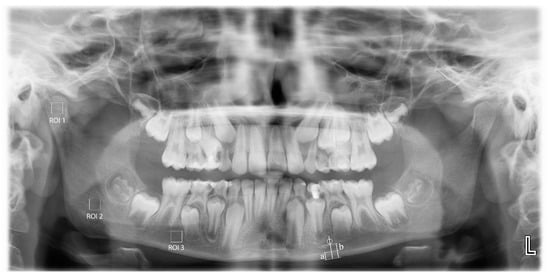

MCW: average width of the mandibular cortical bone (Figure 1(a)) measured through the perpendicular line from mental foramen to the lower margins of mandibula at both sides [21].

PMI: Average ratio of width of the mandibular cortical bone (Figure 1(a)) to the distance between the lower edges of mental foramen and the lower margins of mandibula (Figure 1(b)) bilaterally calculated [22].

All panoramic radiographic measurements were performed by a single trained observer (FS), using the ImageJ 1.3 (National Institutes of Health, Bethesda, MD, USA). The films were scaled 4 times in the x and y planes using bilinear interpolation. The region of interest (ROI) (240 × 240 pixels square) for each patient was standardized for each patient. For the measurements on the panoramic films, 3 different areas were determined: from the geometric center of the right mandibular condyle (ROI1), just below the mandibular canal in the right mandibular angulus region (ROI2), and from the apical level of the right teeth 5 and 6 (ROI3). Anatomical formations such as mandibular canal, cortical bone, lamina dura, and periodontal space from the ROI areas were not included (Figure 1).

Figure 1. Locations of the regions of interest (ROI) selected from the right mandibular condyle (ROI1), angulus (ROI2), and corpus (ROI3) regions in the panoramic radiographs. Mandibular cortical width (a); distance between the inferior borders of the mental foramen and the mandible (b); and panoramic mandibular index (a/b).